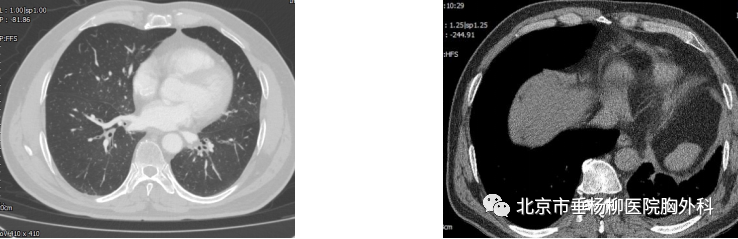

患者男性,60岁,主因“发现左肺下叶占位1月余。以“左肺下叶占位”入院,胸部增强CT:左肺下叶脊柱旁类圆形实性结节影,直径4.5*4.2cm,边界较清晰,增强扫描未见明显强化,可见腹主动脉分支血管进入病灶内。术中叶裂分化不全,左肺下叶与膈肌及纵膈胸膜粘连明显,遂行胸腔镜下左肺下叶切除术,手术历时4小时,完整切除肿物,术后病理回示:叶内型肺隔离症。术后患者恢复良好,术后5天拔出胸腔引流管,术后7天出院。

术后胸部CT(肺窗) 纵膈窗